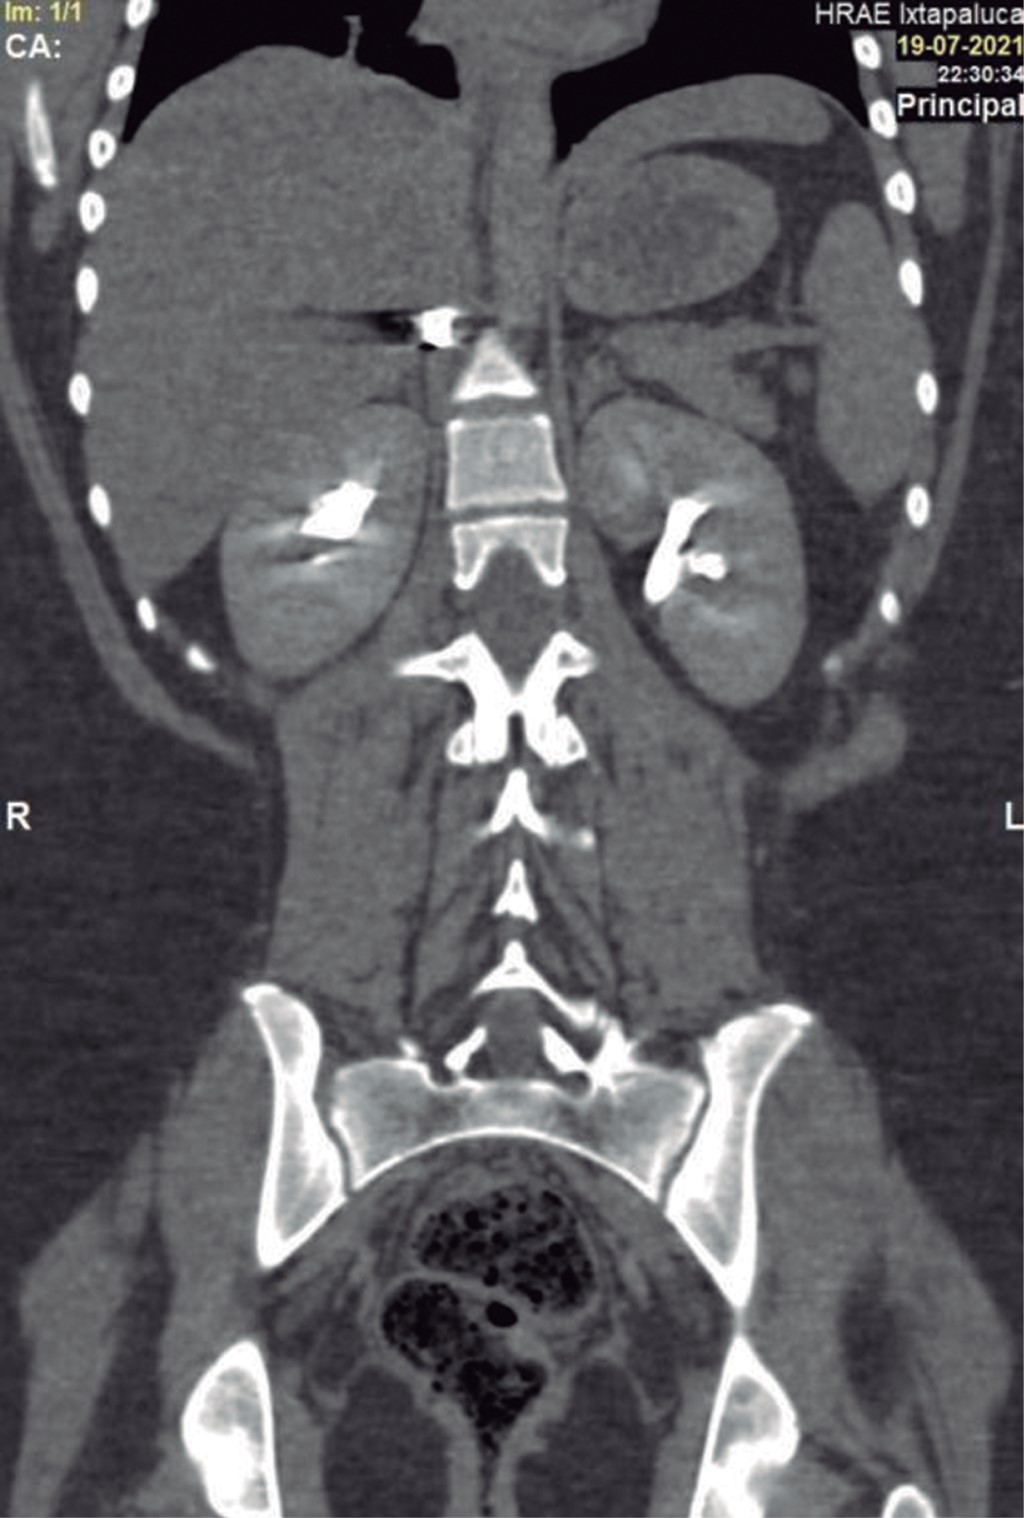

En la exploración física, sus signos vitales fueron los siguientes: frecuencia cardiaca: 74 latidos/minuto; tensión arterial: 98/67 mmHg; frecuencia respiratoria: 19/minuto, temperatura de 36 °C y saturación de oxígeno: 98%. En tórax presentaba un orificio de entrada de PAF en el cuadrante superior externo de la mama derecha (Figura 1), los campos pulmonares estaban bien ventilados. El abdomen era plano, con peristalsis, blando y sin dolor a la palpación. La biometría hemática reportó lo siguiente: hemoglobina: 12.8 g/dl, hematocrito 36.4% y leucocitos: 6,400/ml. La radiografía de tórax descartó neumotórax (Figura 2). Una TC de tórax y abdomen mostró un cuerpo extraño metálico alojado en la línea parasagital derecha a nivel de la doceava vértebra torácica (Figura 3), sin lesión pulmonar ni diafragmática (Figuras 4 y 5); en abdomen se observó un trayecto por PAF con lesión hepática grado IV de 12 cm por 2.3 cm en los segmentos IV, VII y VIII de Couinaud (Figura 5), líquido libre escaso, sin lesión de ningún otro órgano (Figuras 3, 5 y 6). Veinticuatro horas después se le realizó una TC de control, evidenciando la lesión hepática sin colección subcapsular ni extravasación activa a la aplicación del medio de contraste, sin aumento del líquido libre. Ante la correlación de estos hallazgos con la estabilidad clínica, se egresó a la paciente al cuarto día de su ingreso. Sin complicaciones un mes después de su alta.

Figura 6